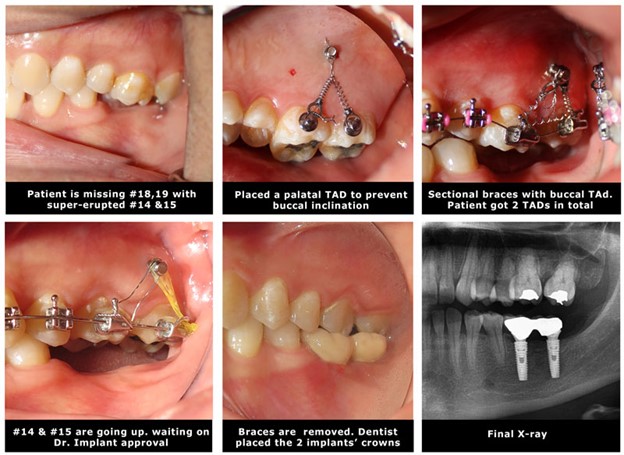

3. Intrusion to correct super-erupted teeth.

Another applications of orthodontic mini implants is to intrude super erupted teeth. The use of temporary anchorage devices for molar intrusion might be done with sectional braces. It is recommended to place two infinity mini implants; in the buccal 8.5 mm long and in the palatal 11 mm to compensate for the thickness of palatal tissue.

4. Close the space of a missing tooth.

Missing teeth are associated with a different degree of bone loss. This bone loss will place a challenge to replace the missing tooth with a traditional dental implant. Another alternative to the dental implant is to close the space with braces if enough teeth exist. This technique will require the use of a Temporary anchorage device TADS to direct the force into the direction of the missing tooth. Make sure the root size of the moving tooth is strong enough “conical roots in molars perform weakly in bodily movement”